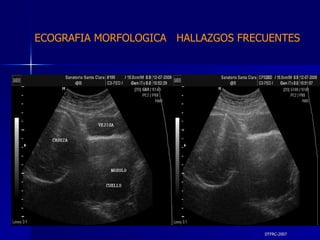

DTFRC-2007 ECOGRAFIA MORFOLOGICA  HALLAZGOS FRECUENTES   MATERIAL Y METODO ES UN ESTUDIO DESCRIPTIVO, RETROSPECTIVO  DE ESTUDIO ECOGRA FICOS REALIZADOS ENTRE MARZO 07 A MARZO 08 EQUIPO DE ALTA RESOLUCION   VOLUSON 730 PRO  MEDISON SA 8000 live MEDISON SA 8000SE CRITERIO DE INCLUSION:   POBLACION GENERAL    GESTACIONES  20 a 24 SEMANAS   UNIVERSO  N 211

DTFRC-2007 ECOGRAFIA MORFOLOGICA  HALLAZGOS FRECUENTES   SISTEMA NERVIOSO CENTRAL TOTAL  8  26 % 1 HIDROCEFALIA 2 VENTRICULO MEGALIA 4 QUISTE DE PLEXO COROIDEO 1 ANENCEFALIA

DTFRC-2007 ECOGRAFIA MORFOLOGICA  HALLAZGOS FRECUENTES   GENITOURINARIA DISPLASIA RENAL MULTIQUISTICA  3 HIDRONEFROSIS  2 QUISTE DE OVARIO FETAL  1 SISTEMA DIGESTIVO DILATACION INTESTINAL  2  SISTEMA ESQUELETICO   PIE BOT  2  20 % 6 % 6 %